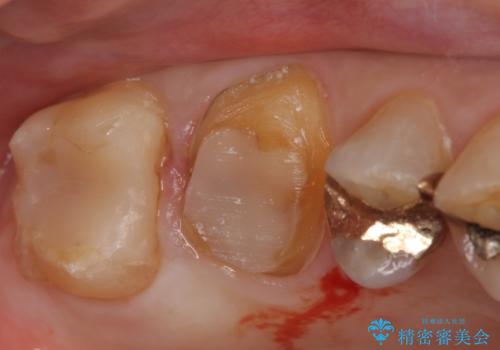

- 冷たいものがしみる右上の奥歯を治療して欲しいといらっしゃった方の症例です。

右上6,7の金歯を外したところ、虫歯が歯茎より深い位置まで進行していたため歯周外科を行いました。

その後歯茎の回復を待ち、オールセラミッククラウンおよびセラミックインレーによる補綴・修復を行いました。